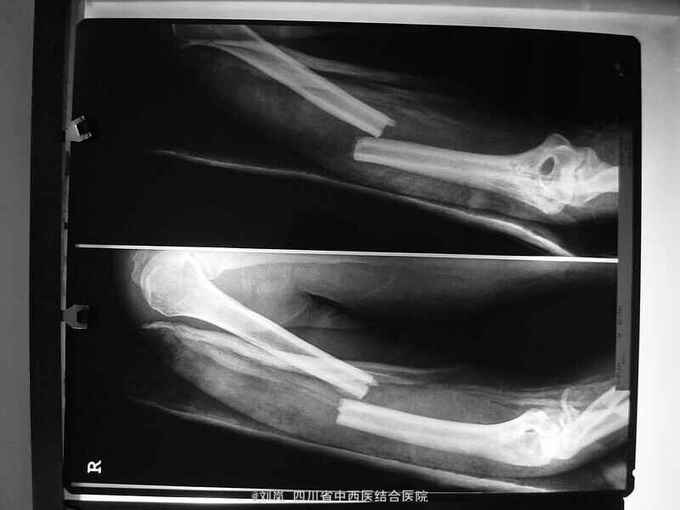

查体:T 37.9℃、P 110次/分、R 22次/分、BP 126/80mmHg;一般情况:神清,烦躁,发育正常,平车推入,查体不合作。头额顶部见横行挫伤,头皮肿胀、压痛明显,未扪及骨擦感,右上下睑肿胀青紫,左面部见擦挫伤,双侧瞳孔等大等圆,直径约3mm,对光反射迟钝,鼻腔无溢液,左耳廓见擦伤,外耳道无异常分泌物,双唇肿胀,无紫绀及苍白,齿齐,扁桃体不大,颈软,气管居中,甲状腺不大;胸廓对称无畸型,右侧胸胁部压痛明显,似可扪及骨擦感,呼吸动度基本一致,双肺叩呈清音,双肺呼吸音粗,双肺未闻及干、湿性罗音;心界叩诊不大,心率110次/分,律齐,各瓣膜听诊区未闻及病理性杂音。腹平,未见肠型及蠕动波,未见浅静脉曲张,肝脾未扪及,腹肌紧张,压痛,反跳痛明显,无移动性浊音,肝肾区无叩痛,肠鸣音3次/分。脊柱下肢无畸型,活动正常,右膝前见一约5cm挫裂伤口,深及髌骨,未扪及骨擦感,右上臂及右前臂夹板外固定中,桡动脉搏动可,末梢循环可,肛门及外生殖器未查,排泄物未见。神经系统检查生理反射存在,病理反射未引出。 患者入院急诊行了剖腹探查术等治疗;2周后外科病情平稳,转骨科治疗。转入查体:头额部无畸形,右眼睑肿胀减轻,仍可见双眼周围青紫瘀斑减轻,两侧瞳孔等大等圆,直径3mm,对光反射灵敏,颈软,无抵抗,布鲁金斯基征(-),双侧胸廓对称,无畸形,双侧呼吸动度一致;腹中度见一大约10cm手术切口瘢痕,已经愈合,切口对合良好,未见异常渗血渗液,右下腹原引流管拔除处创口未愈合,经换药可见创口大约1.5*2.5cm2,创口基底部乳白色分泌物,无血性及脓性分泌物,创口周围轻微肿胀,无皮色改变,无皮温升高,无波动感,压痛(+),无反跳痛,无肌紧张,无移动性浊音;骨盆分离挤压试验(- );右上肢石膏托固定良好,拆开石膏见:右上臂外侧见一大约2*2.5cm的创口,周围无红肿,无皮温皮色改变,创面红润,未见异常渗血渗液,未见骨质外露,右上臂中段及右双前臂中下段畸形,压痛明显,可触及明显骨擦感及异常活动,右上肢纵向叩击痛(++),右上肢及右前臂旋转功能活动障碍,右腕关节及右手拇指不能主动背伸活动,右前臂中下段以下皮肤感觉功能障碍,右手呈轻度屈曲挛缩畸形,无法主动伸直及主动握拳,指端血运正常。 辅助检查: DR示:1.腹腔内游离气体 2.右肱骨中段骨折 3.右尺桡骨中下段粉碎性骨折。 CT示:1.右侧顶叶点状高密度影,脑挫裂伤?右侧额部及左侧额顶部头皮血肿。2.右肺斑片及斑点状阴影,感染灶?3.右侧约第7、8肋骨可疑骨折。4.腹腔内可疑积气:盆腔可疑少量积液:膀胱内片状较高密度影,积血? 彩色多普勒提示:膈下游离气体,少量腹腔积液。

入院诊断: 1、高处坠落伤 2、脑挫裂伤 3、小肠部分坏死 小肠穿孔 肠系膜挫伤 4、右肱骨中段骨折 5、右尺桡骨中下段骨折 6、腹腔积气 7、右第7、8肋可疑骨折 8、轻度贫血 9、全身多发皮肤软组织挫伤 转入诊断: 1、高处坠落伤 2、右肱骨中段骨折 3、右侧尺桡骨中下段粉碎性骨折 4、脑挫裂伤(右,顶叶) 5、右侧桡神经损伤 6、右侧正中神经损伤 7、右侧尺神经损伤 8、右前臂Volkmann缺血性肌痉挛 9、右侧第7肋、左侧第8肋骨骨折 10、小肠部分切除、小肠修补、阑尾切除术后 11、右膝清创缝合术后 12、腹腔积气 13、轻度贫血 14、全身多发皮肤软组织挫裂伤 治疗: 患者急诊入院后,予完善检查,诊断明确,完善急诊手术准备,急诊在全麻下行了“剖腹探查:小肠坏死部分切除、小肠修补+阑尾切除术+腹腔引流术”,术后在ICU继续抗炎、止血、补液脱水监护对症治疗,并请骨科会诊后予右上肢石膏固定。 术后两周外科病情平稳,再次请骨科会诊后转骨科治疗。转入后进一步完善相关检查及术前准备,诊断明确后,在“全麻”下行了"右肱骨中段骨折切开复位内固定、右尺桡骨中下段骨折切开复位内固定术+植骨术、右侧桡神经损伤探查术",术中见桡神经挫伤明显,局部瘀血及增生组织包裹,予松解处理。术后予消肿、止痛、营养神经、预防感染等对症支持治疗,结合针灸、理疗、中药口服及康复治疗。术后伤口愈合及拆线后,予中药熏洗治疗,配合患肢主被动功能康复锻炼,住院2个月,患肢功能活动明显改善,病情好转出院。